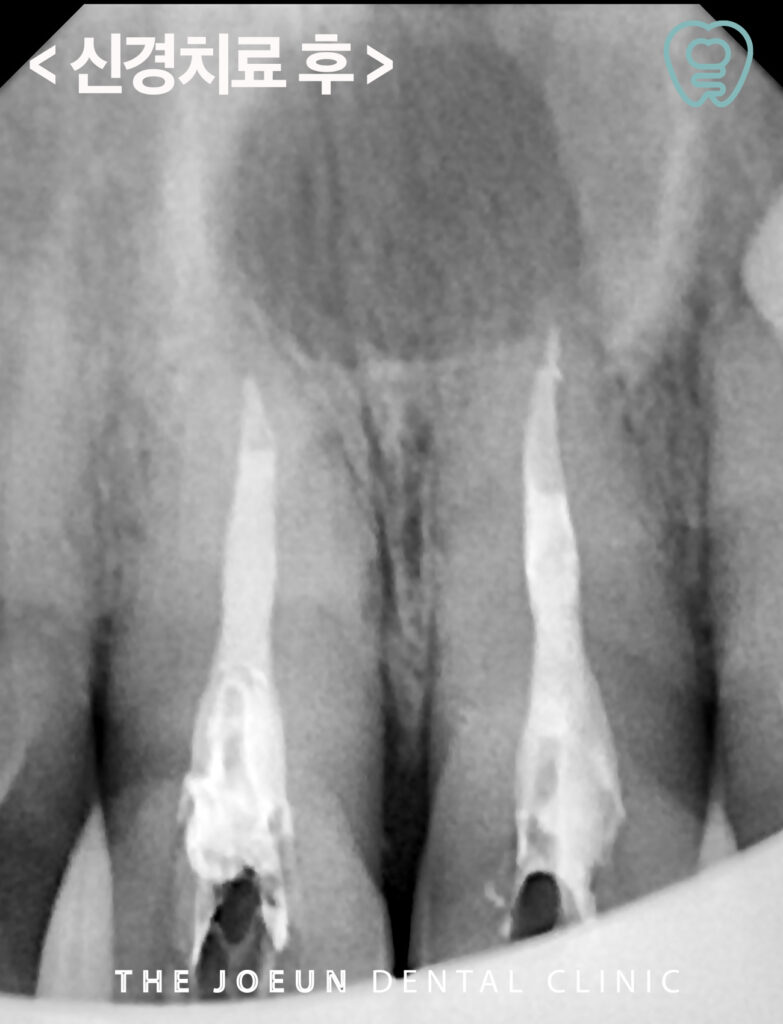

낭종 적출술을 진행하기 전 신경치료를 먼저 완료하였습니다.

모든 방사선 검사에서 경계가 뚜렷이 보이는 낭종이 관찰되었고 낭종적출술을 진행하기로 계획을 수립하였습니다.